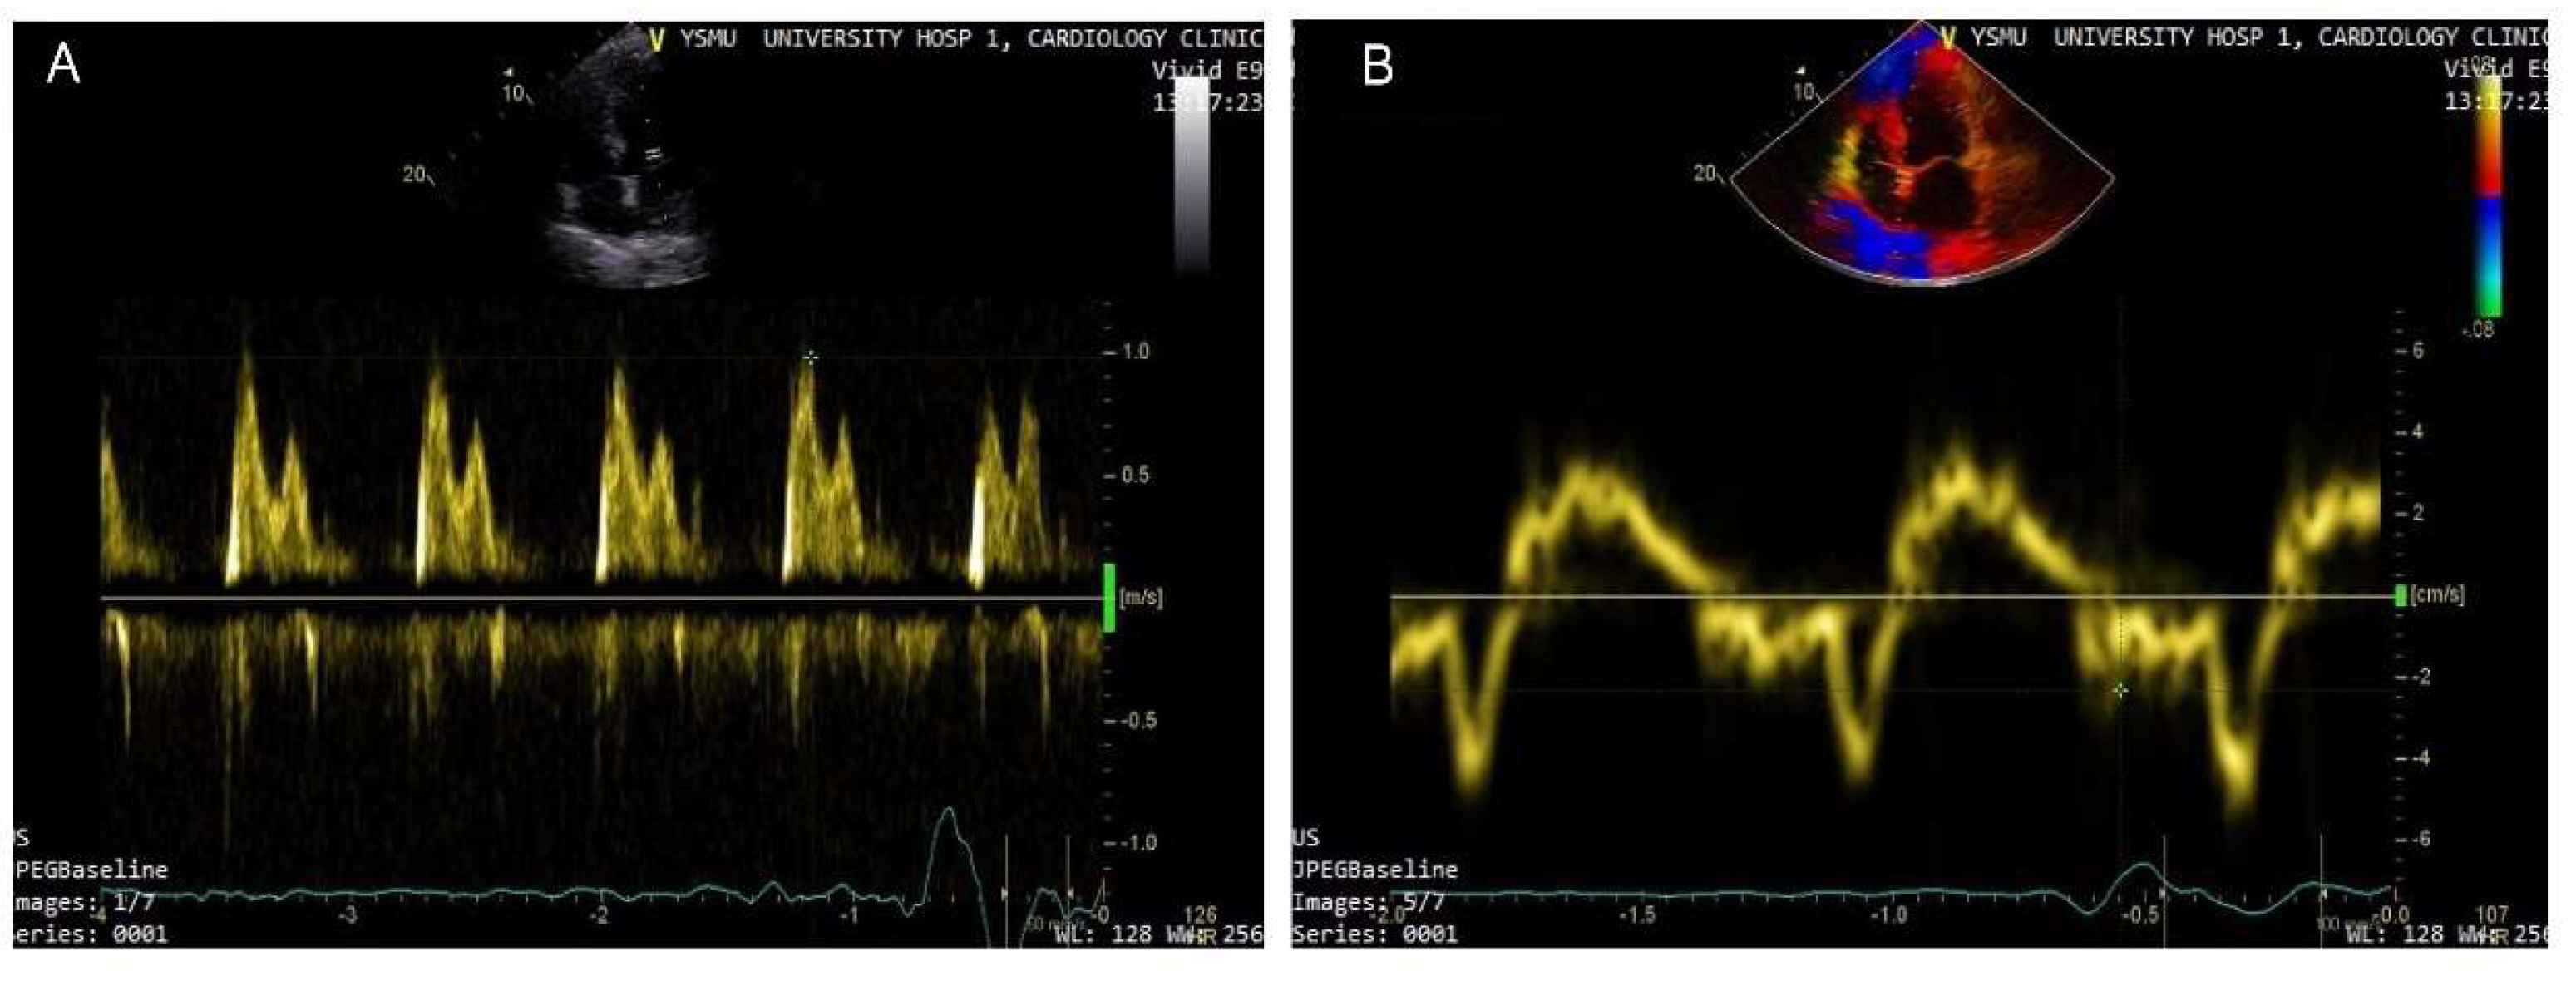

- Nagueh, S.F.; Smiseth, O.A.; Appleton, C.P.; Byrd, B.F., 3rd; Dokainish, H.; Edvardsen, T.; Flachskampf, F.A.; Gillebert, T.C.; Klein, A.L.; Lancellotti, P.; et al. Recommendations for the Evaluation of Left Ventricular Diastolic Function by Echocardiography: An Update from the American Society of Echocardiography and the European Association of Cardiovascular Imaging. J. Am. Soc. Echocardiogr. 2016, 29, 277–314. [Google Scholar] [CrossRef] [PubMed]

- Ommen, S.R.; Nishimura, R.A.; Appleton, C.P.; Miller, F.A.; Oh, J.K.; Redfield, M.M.; Tajik, A.J. Clinical utility of Doppler echocardiography and tissue Doppler imaging in the estimation of left ventricular filling pressures: A comparative simultaneous Doppler-catheterization study. Circulation 2000, 102, 1788–1794. [Google Scholar] [CrossRef]

- Park, J.H.; Marwick, T.H. Use and Limitations of E/e’ to Assess Left Ventricular Filling Pressure by Echocardiography. J. Cardiovasc. Ultrasound 2011, 19, 169–173. [Google Scholar] [CrossRef]

- Lancellotti, P.; Galderisi, M.; Edvardsen, T.; Donal, E.; Goliasch, G.; Cardim, N.; Magne, J.; Laginha, S.; Hagendorff, A.; Haland, T.F.; et al. Echo-Doppler estimation of left ventricular filling pressure: Results of the multicentre EACVI Euro-Filling study. Eur. Heart J. Cardiovasc. Imaging 2017, 18, 961–968. [Google Scholar] [CrossRef]